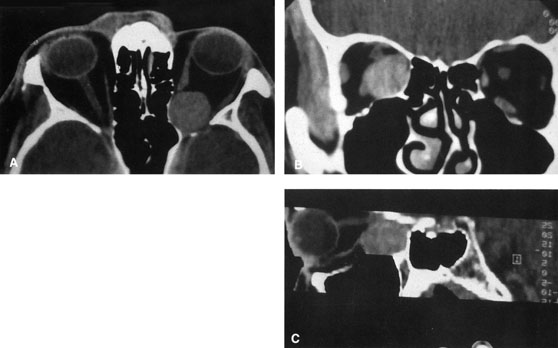

TRANSANTRAL ORBITOTOMY Lesions in the subperiosteal space that involve the orbital floor and roof of the maxillary sinus can be approached through an intraoral incision in the buccal sulcus above the upper canine incisors (Fig. 19). Dissection is carried through mucosa and soft tissue to the periosteum over the face of the maxilla. Dissection is carried superiorly in the subperiosteal plane to just below the inferior orbital rim. Care must be taken to identify the infraorbital nerve as it exits the foramen just below the rim. Osteotomies then are made in the face of the maxilla, and the underlying maxillary sinus is exposed. The sinus mucosa is excised and the roof of the sinus exposed in this fashion. Removal of the sinus roof (the orbital floor) allows exposure of the inferior periorbita. Care must be taken to avoid damage to the infraorbital nerve that runs within the bone of the floor. The inferior rectus muscle is encountered immediately above the periorbita, and it must be protected and retracted during deeper orbital dissection.